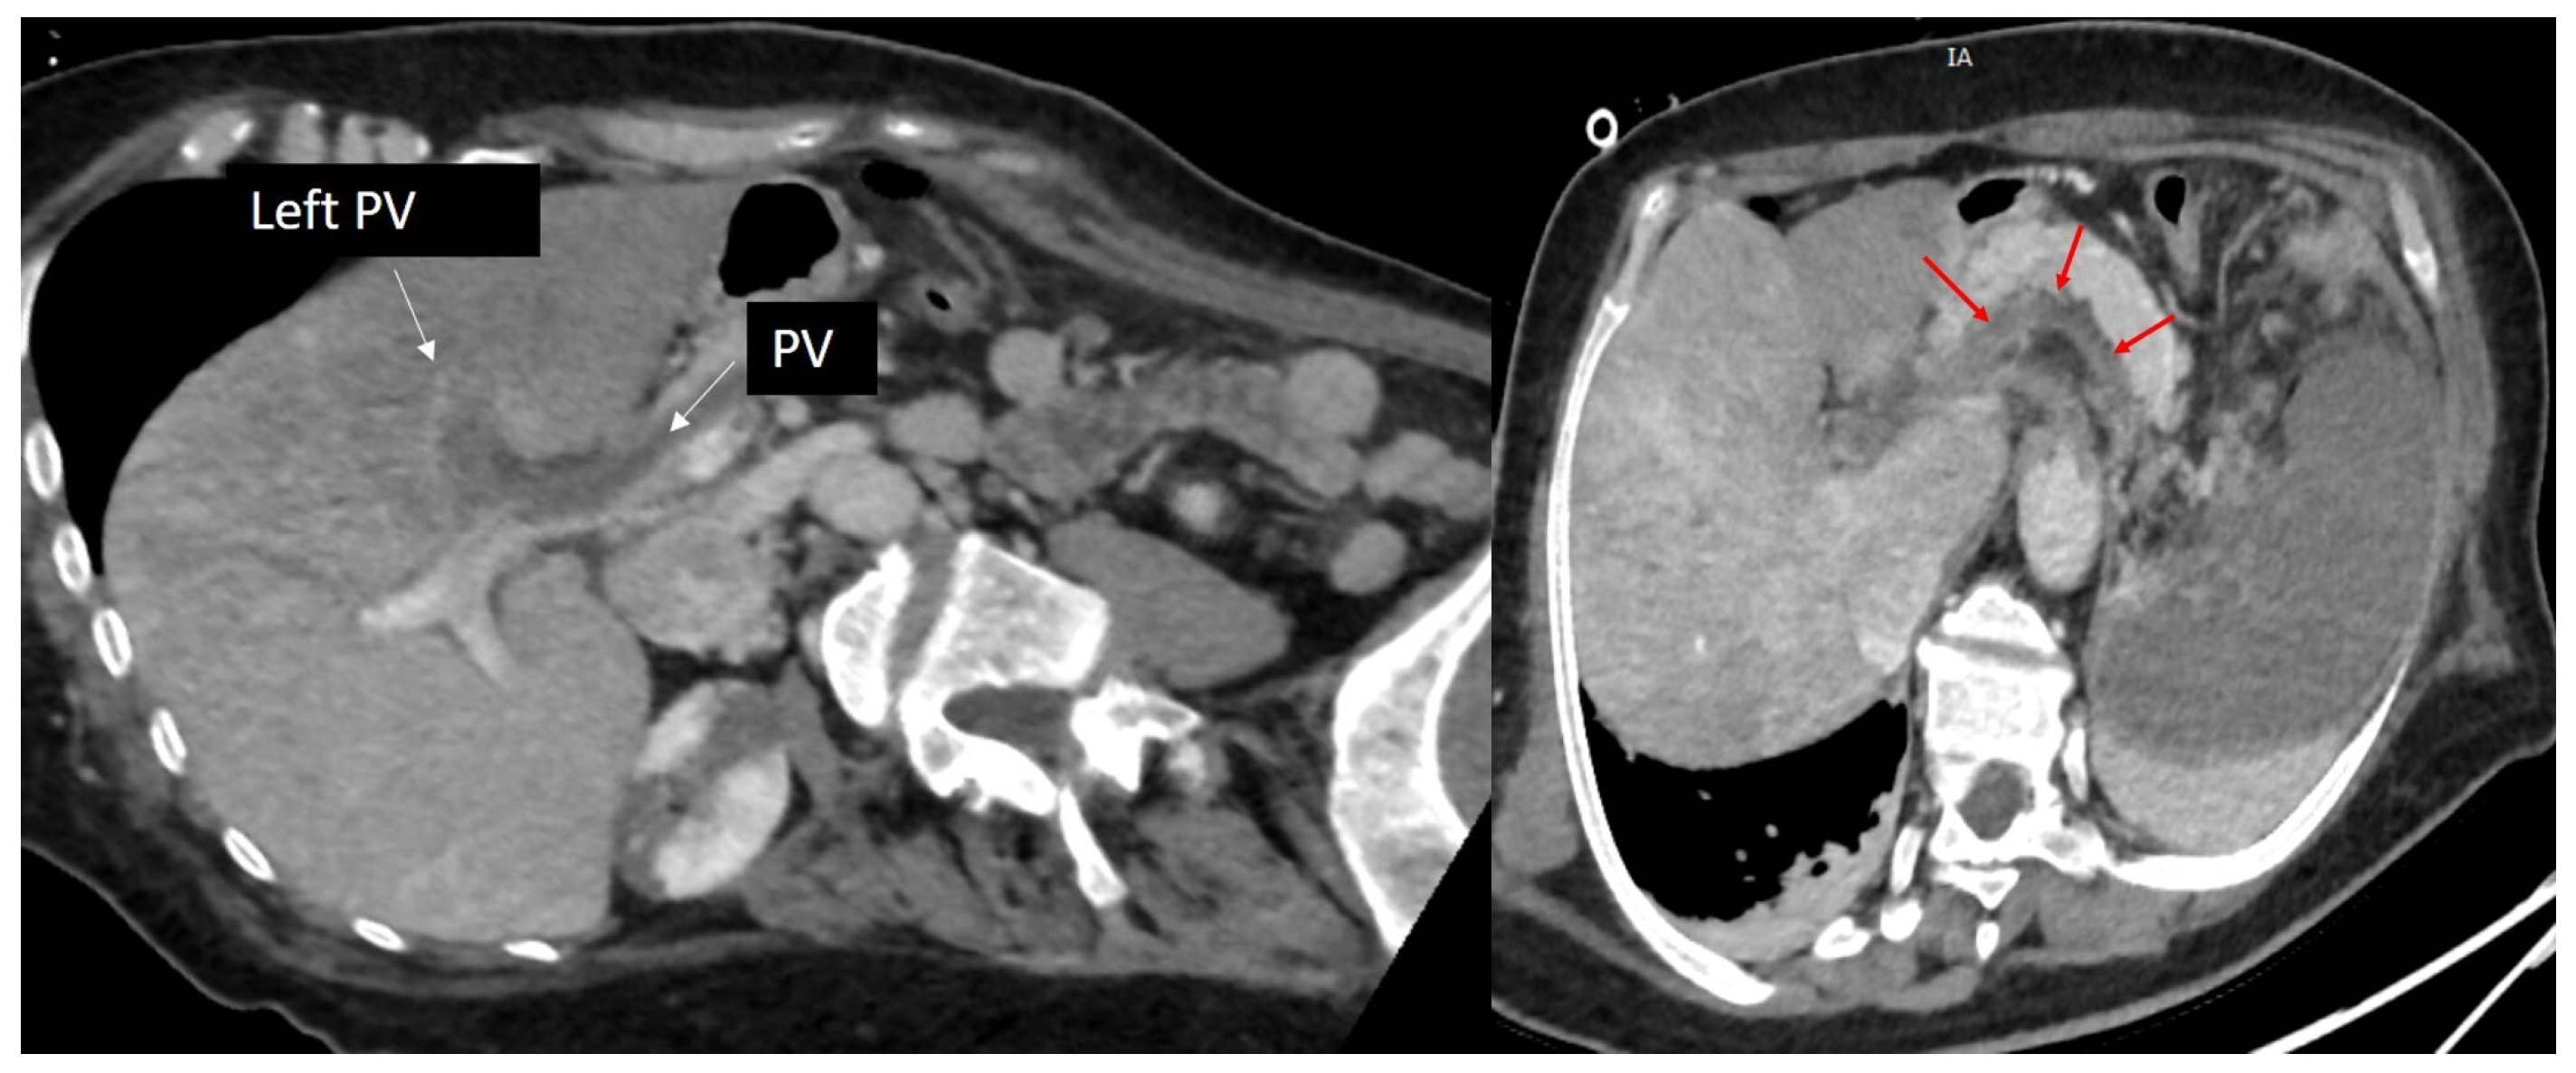

2. Case Presentation